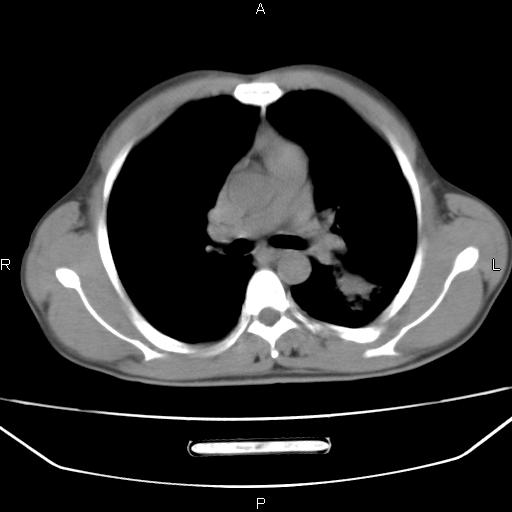

患者,男,40岁。间断发热,咳嗽二十余日。体温最高达38.9° 在当地诊所抗炎治疗三天后体温降至正常,患者自行停药。今又发热。胸片示,左下肺阴影。

左下肺片状高密度影,境界模糊,密度不均,考虑感染性病变可能性大,建议抗炎治疗后复查。左肺门增大,不除外占位性病变,必要时支气管镜检。